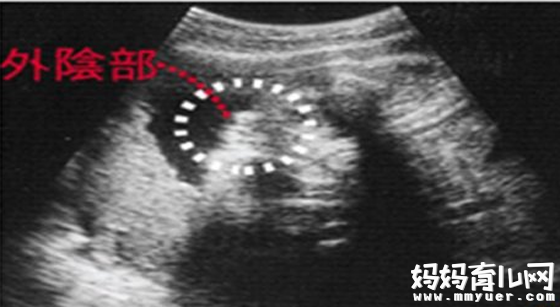

女宝宝的b超图:

三条白线是明显的女宝特征,如果没有看到明显的三条白线,就看两腿之间有没有突出的东东,且中间有小凹槽的,就是女宝